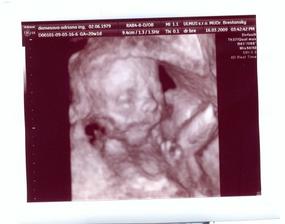

Teraz nás už konečne čaká 3Dčko v pondelok....a hádam budeme vidieť aj čiaročku alebo paličku.

16.3.2009 3D: 20tt+1, a je to tam! čiaročka!!! takže vraj na milión % bude dievčatko. s taťuldom sa neskutočne tešíme na našu bambuľku!